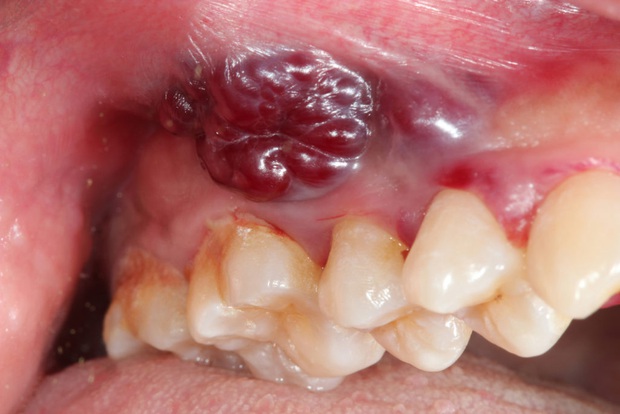

Ngoài ra, vết loét này cũng sẽ ngày càng lan rộng ra, gây đau nhức và nổi hằn các mạch máu rõ rệt hơn.